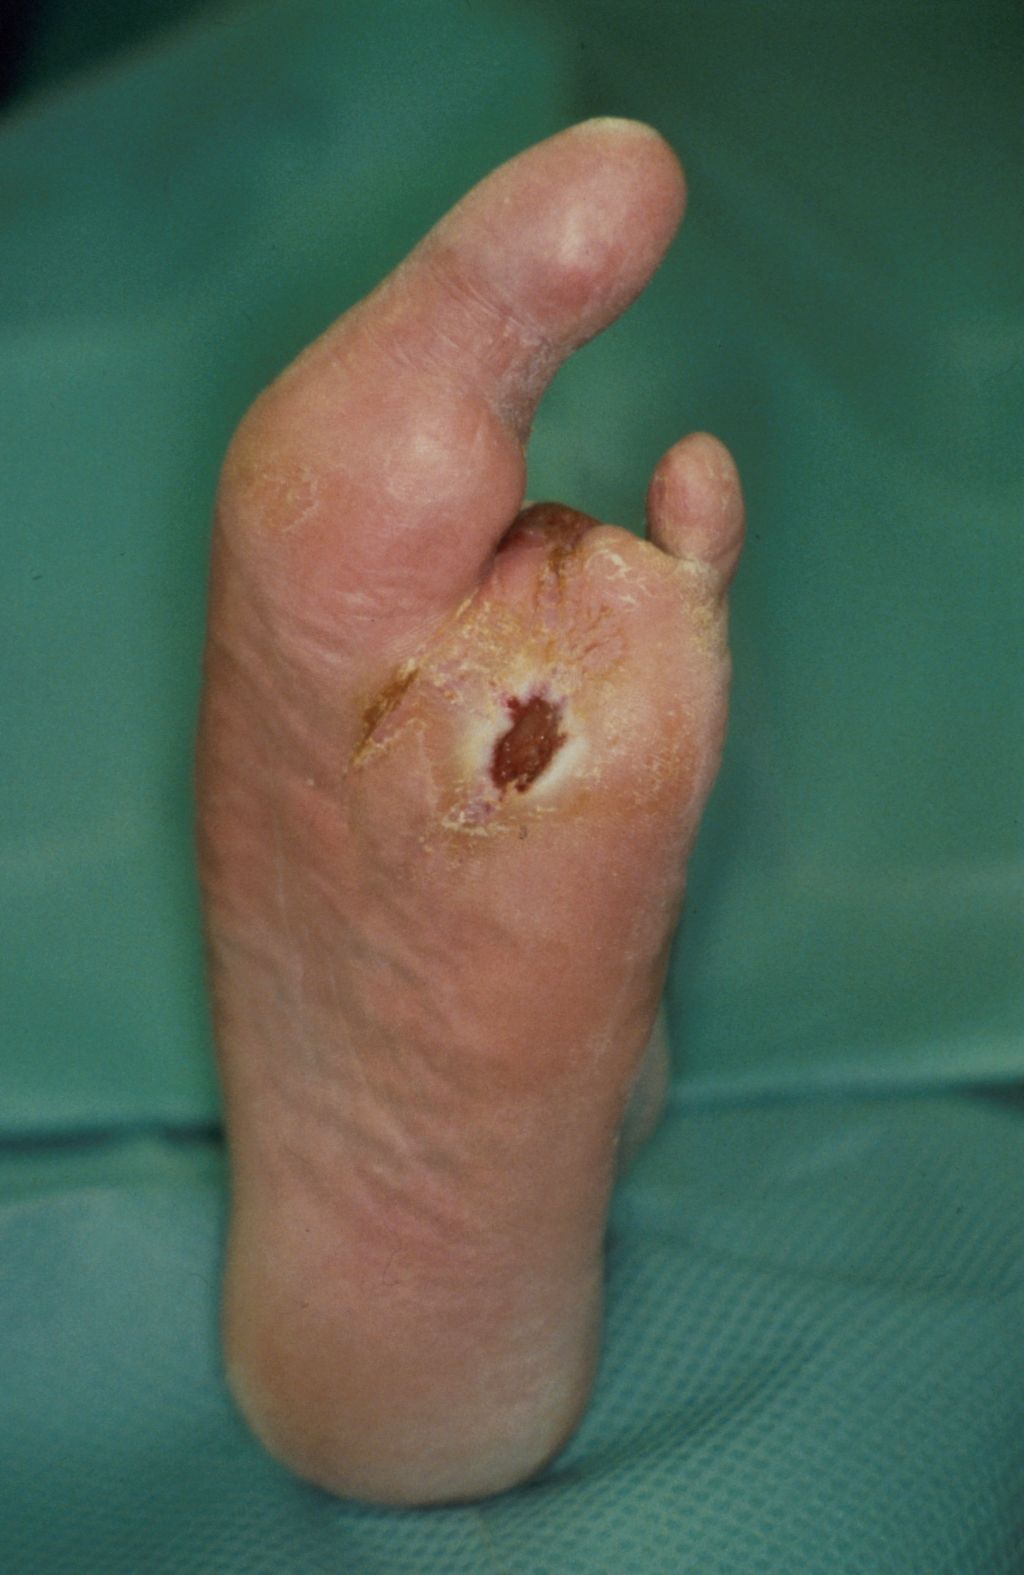

Neuropathische voet bij lepra

Het grote probleem bij lepra is de (meestal irreversibele)

neuropathie

die wordt veroorzaakt door de immuunreactie. De neuropathie uit zich als een

verminderde sensibiliteit in de laesies, maar later ook in perifere neuropathie,

niet alleen sensibel maar ook motorisch. De sensibiliteit voor druk kan worden

trauma, en aan de tenen en voetzolen door druk

of knellende schoenen. Het voetgewelf zakt in waardoor er een bolle voet ontstaat

met nieuwe drukpunten midden onder de voet. De

ingezakte voet

wordt vaak een

Charcot voet of

rockerbottom

voet genoemd. De tenen gaan in een dwangstand staan en krijgen

nieuwe drukpunten aan de bovenkant en aan de onderkant. De

wondjes

en

drukulcera zijn vaak bedekt met een dikke laag

eelt (

callus), gaan dieper dan aan de buitenkant zichtbaar

is en kunnen infecteren en overgaan in een

osteomyelitis.

Vaak moeten tenen en vingers worden geamputeerd vanwege infectie en osteomyelitis.

![Neuropathische voet bij lepra (click on photo to enlarge) [source: www.huidziekten.nl] Neuropathische voet bij lepra](../../../images/neuropathische-voet-lepra-1z.jpg) |

| neuropathische

voet |